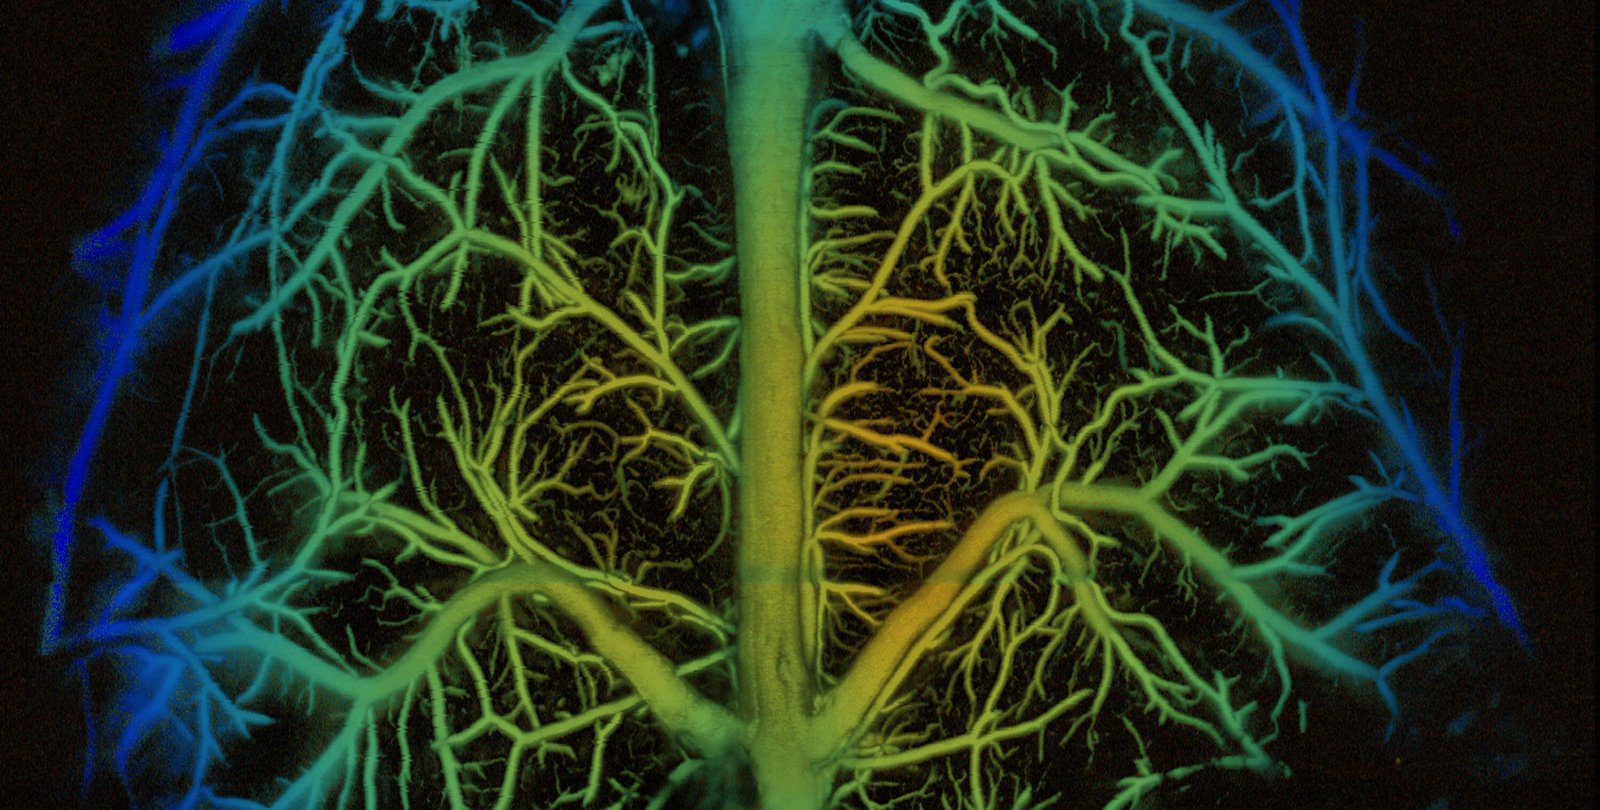

That greater depth of field was demonstrated by the researchers in two ways: imaging fresh organ samples using an ultraviolet laser and imaging in vivo mouse brain vasculature using a blue laser.

In a new paper in the journal Nature Photonics, Wang and his research team show how they developed a new variant of PAM called needle-shaped beam photoacoustic microscopy, or NB-PAM, which that has a depth of field nearly 14 times greater than what was achievable before. This means NB-PAM can create 3-D imagery of samples without refocusing and better image samples with uneven surfaces.

NB-PAM improves its depth of field over its related PAM technologies by using a beam of laser light that is longer and thinner, hence "needle shaped." This change in the optical characteristics of the beam avoids some of the drawbacks associated with other attempts to increase the depth of field of PAM technology, such as working more slowly, or requiring more computer processing power.